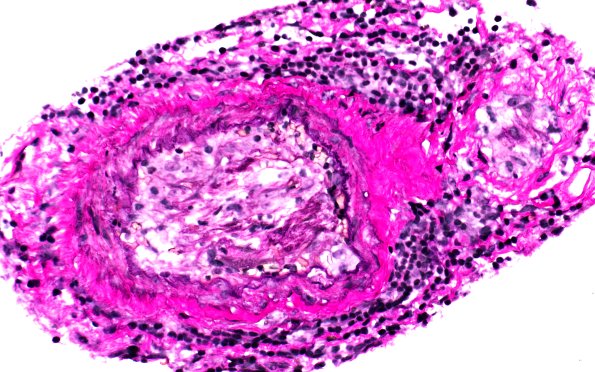

Vasculitis - PACNS

The vessel shows disruption of the internal elastic lamina and the vessel lumen may be organized. (Elastin)